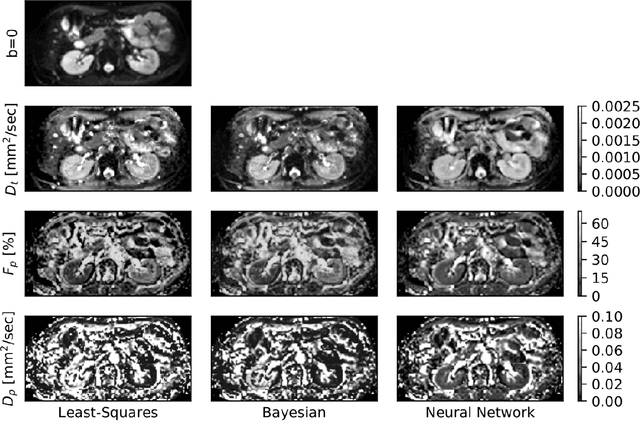

Abstract:Purpose: This prospective clinical study assesses the feasibility of training a deep neural network (DNN) for intravoxel incoherent motion (IVIM) model fitting to diffusion-weighted magnetic resonance imaging (DW-MRI) data and evaluates its performance. Methods: Approval for this study was obtained by the responsible ethics committees and written informed consent was obtained from all accrued subjects. In May 2011, ten male volunteers (age range: 29 to 53 years, mean: 37 years) underwent DW-MRI of the upper abdomen on 1.5T and 3.0T magnetic resonance scanners. Regions of interest in the left and right liver lobe, pancreas, spleen, renal cortex, and renal medulla were delineated independently by two readers. DNNs were trained for IVIM model fitting using these data; results were compared to least-squares and Bayesian approaches to IVIM fitting. Intraclass Correlation Coefficients (ICC) were used to assess consistency of measurements between readers. Intersubject variability was evaluated using Coefficients of Variation (CV). The fitting error was calculated based on simulated data and the average fitting time of each method was recorded. Results: DNNs were trained successfully for IVIM parameter estimation. This approach was associated with high consistency between the two readers (ICCs between 50 and 97%), low intersubject variability of estimated parameter values (CVs between 9.2 and 28.4), and the lowest error when compared with least-squares and Bayesian approaches. Further, fitting by DNNs was several orders of magnitude quicker than the other methods. Conclusion: DNNs are recommended for accurate and robust IVIM model fitting to DW-MRI data. Suitable software is available at (1).